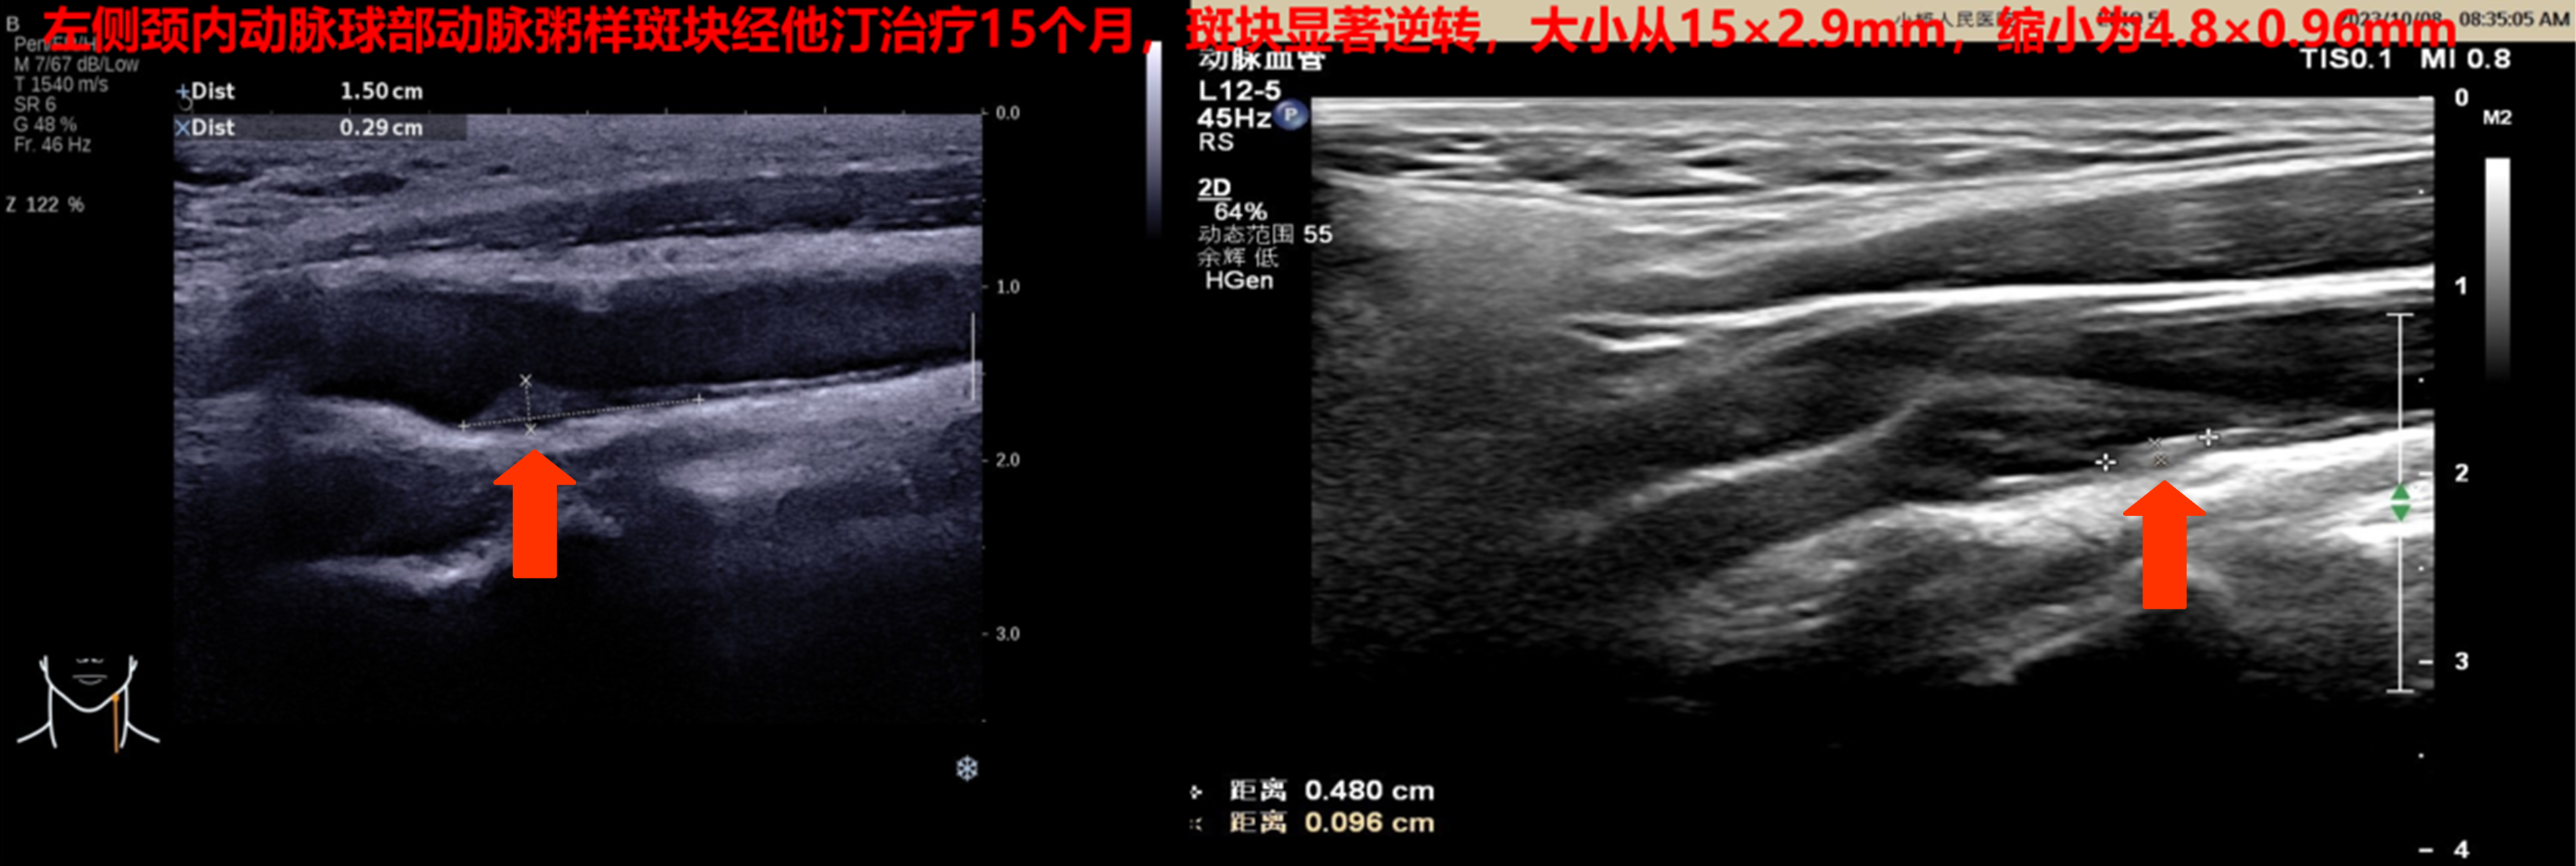

8、他汀治疗